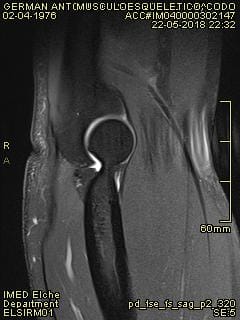

¿Quién me puede echar una mano con una resonancia magnética de tedon de bíceps en codo?

la mutua no se pone de acuerdo con el hospital y me tienen mareado, ¿alguien me echa una mano para saber lo que puedo tener en el codo? Dispongo de más fotos, pero no se cual indicar para que puedan ver algo. Muchas gracias de antemano